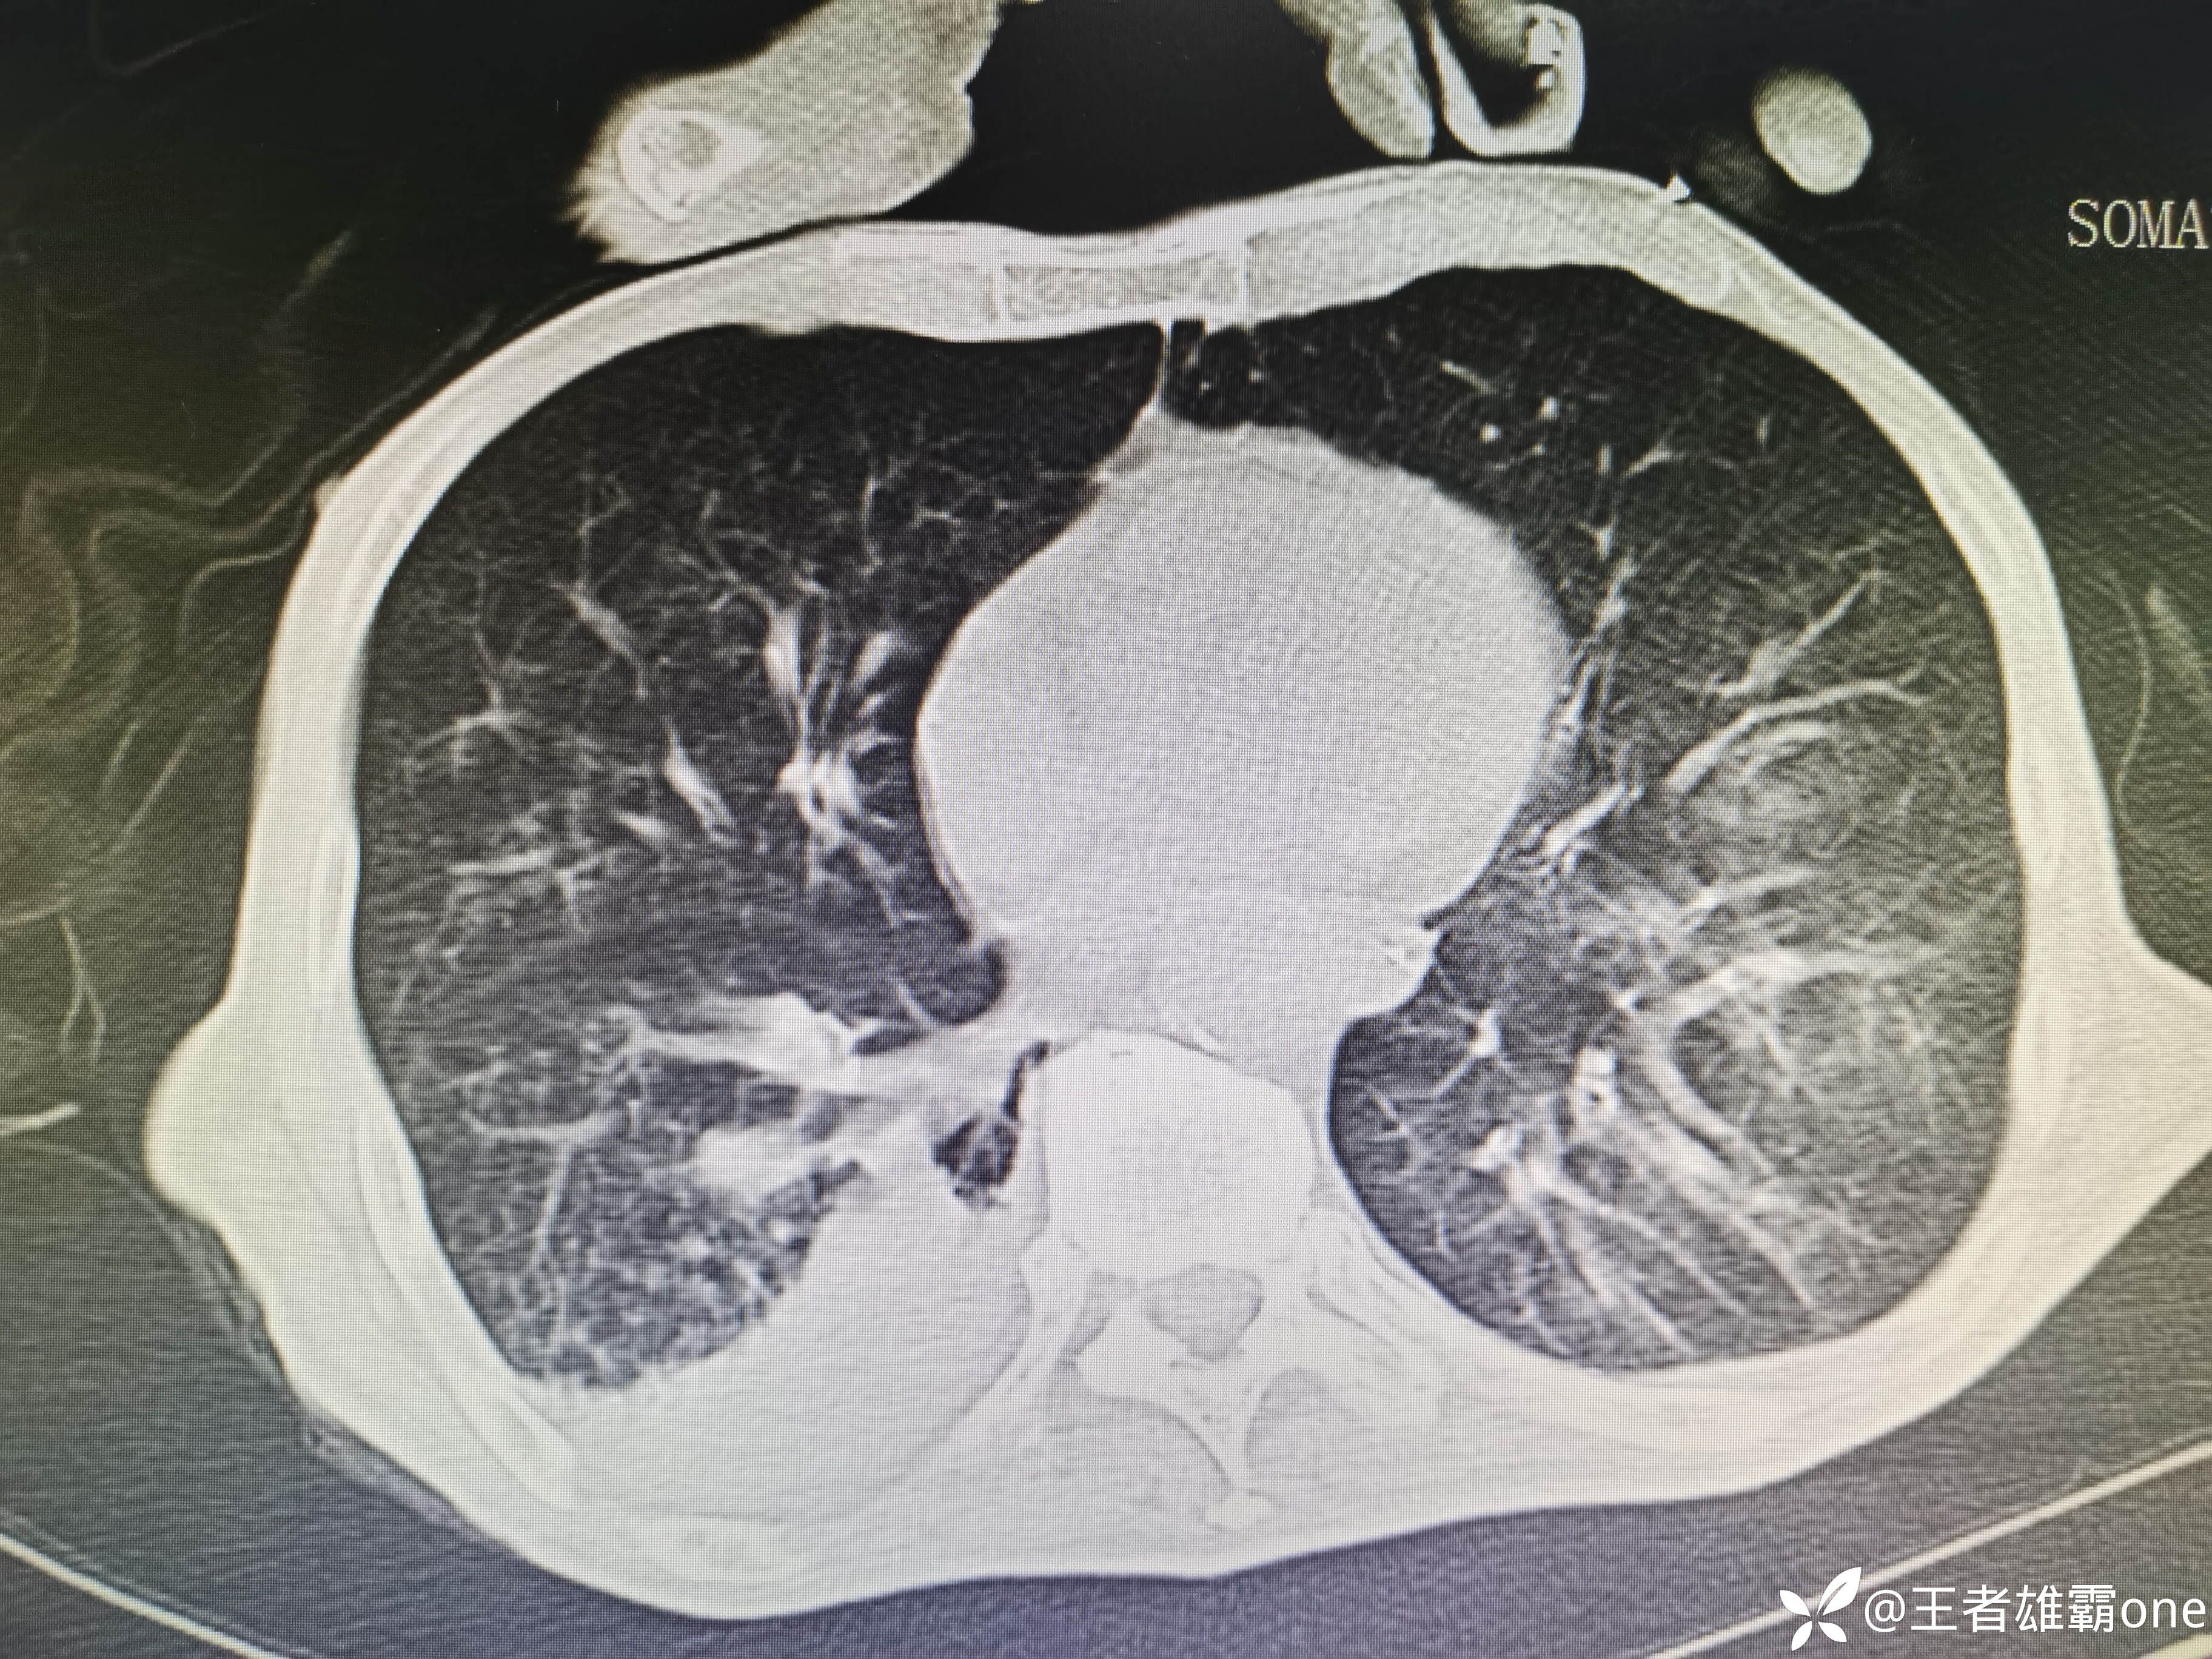

入院时胸部CT:

具体图片: